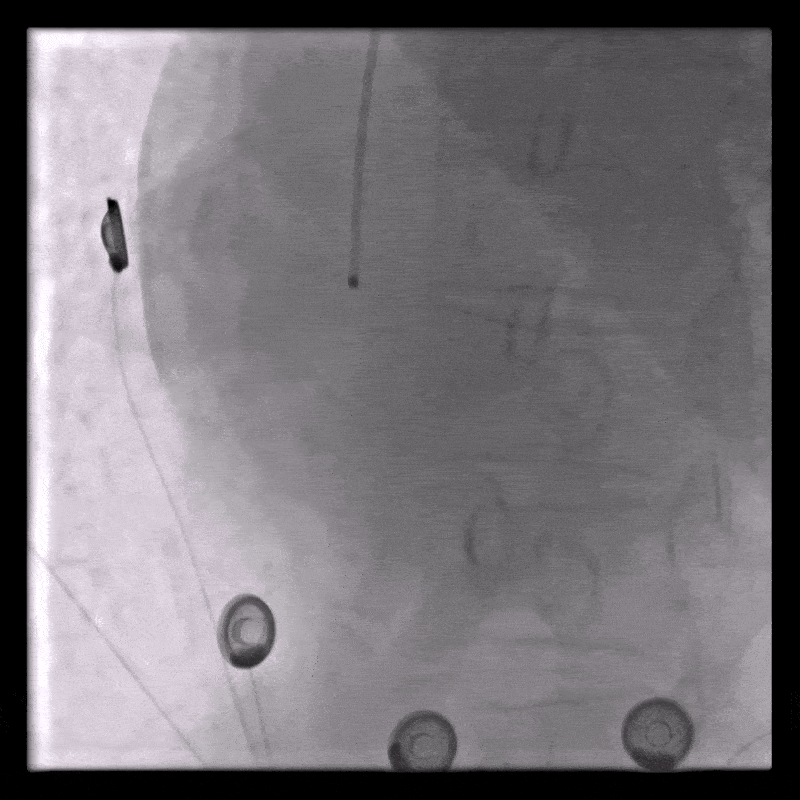

Due to persistent severe LV dysfunction and risk of cardiogenic shock, Impella 5.5 was implanted on day 3 for LVunloading.

Correct position was assessed by TEE and CXR